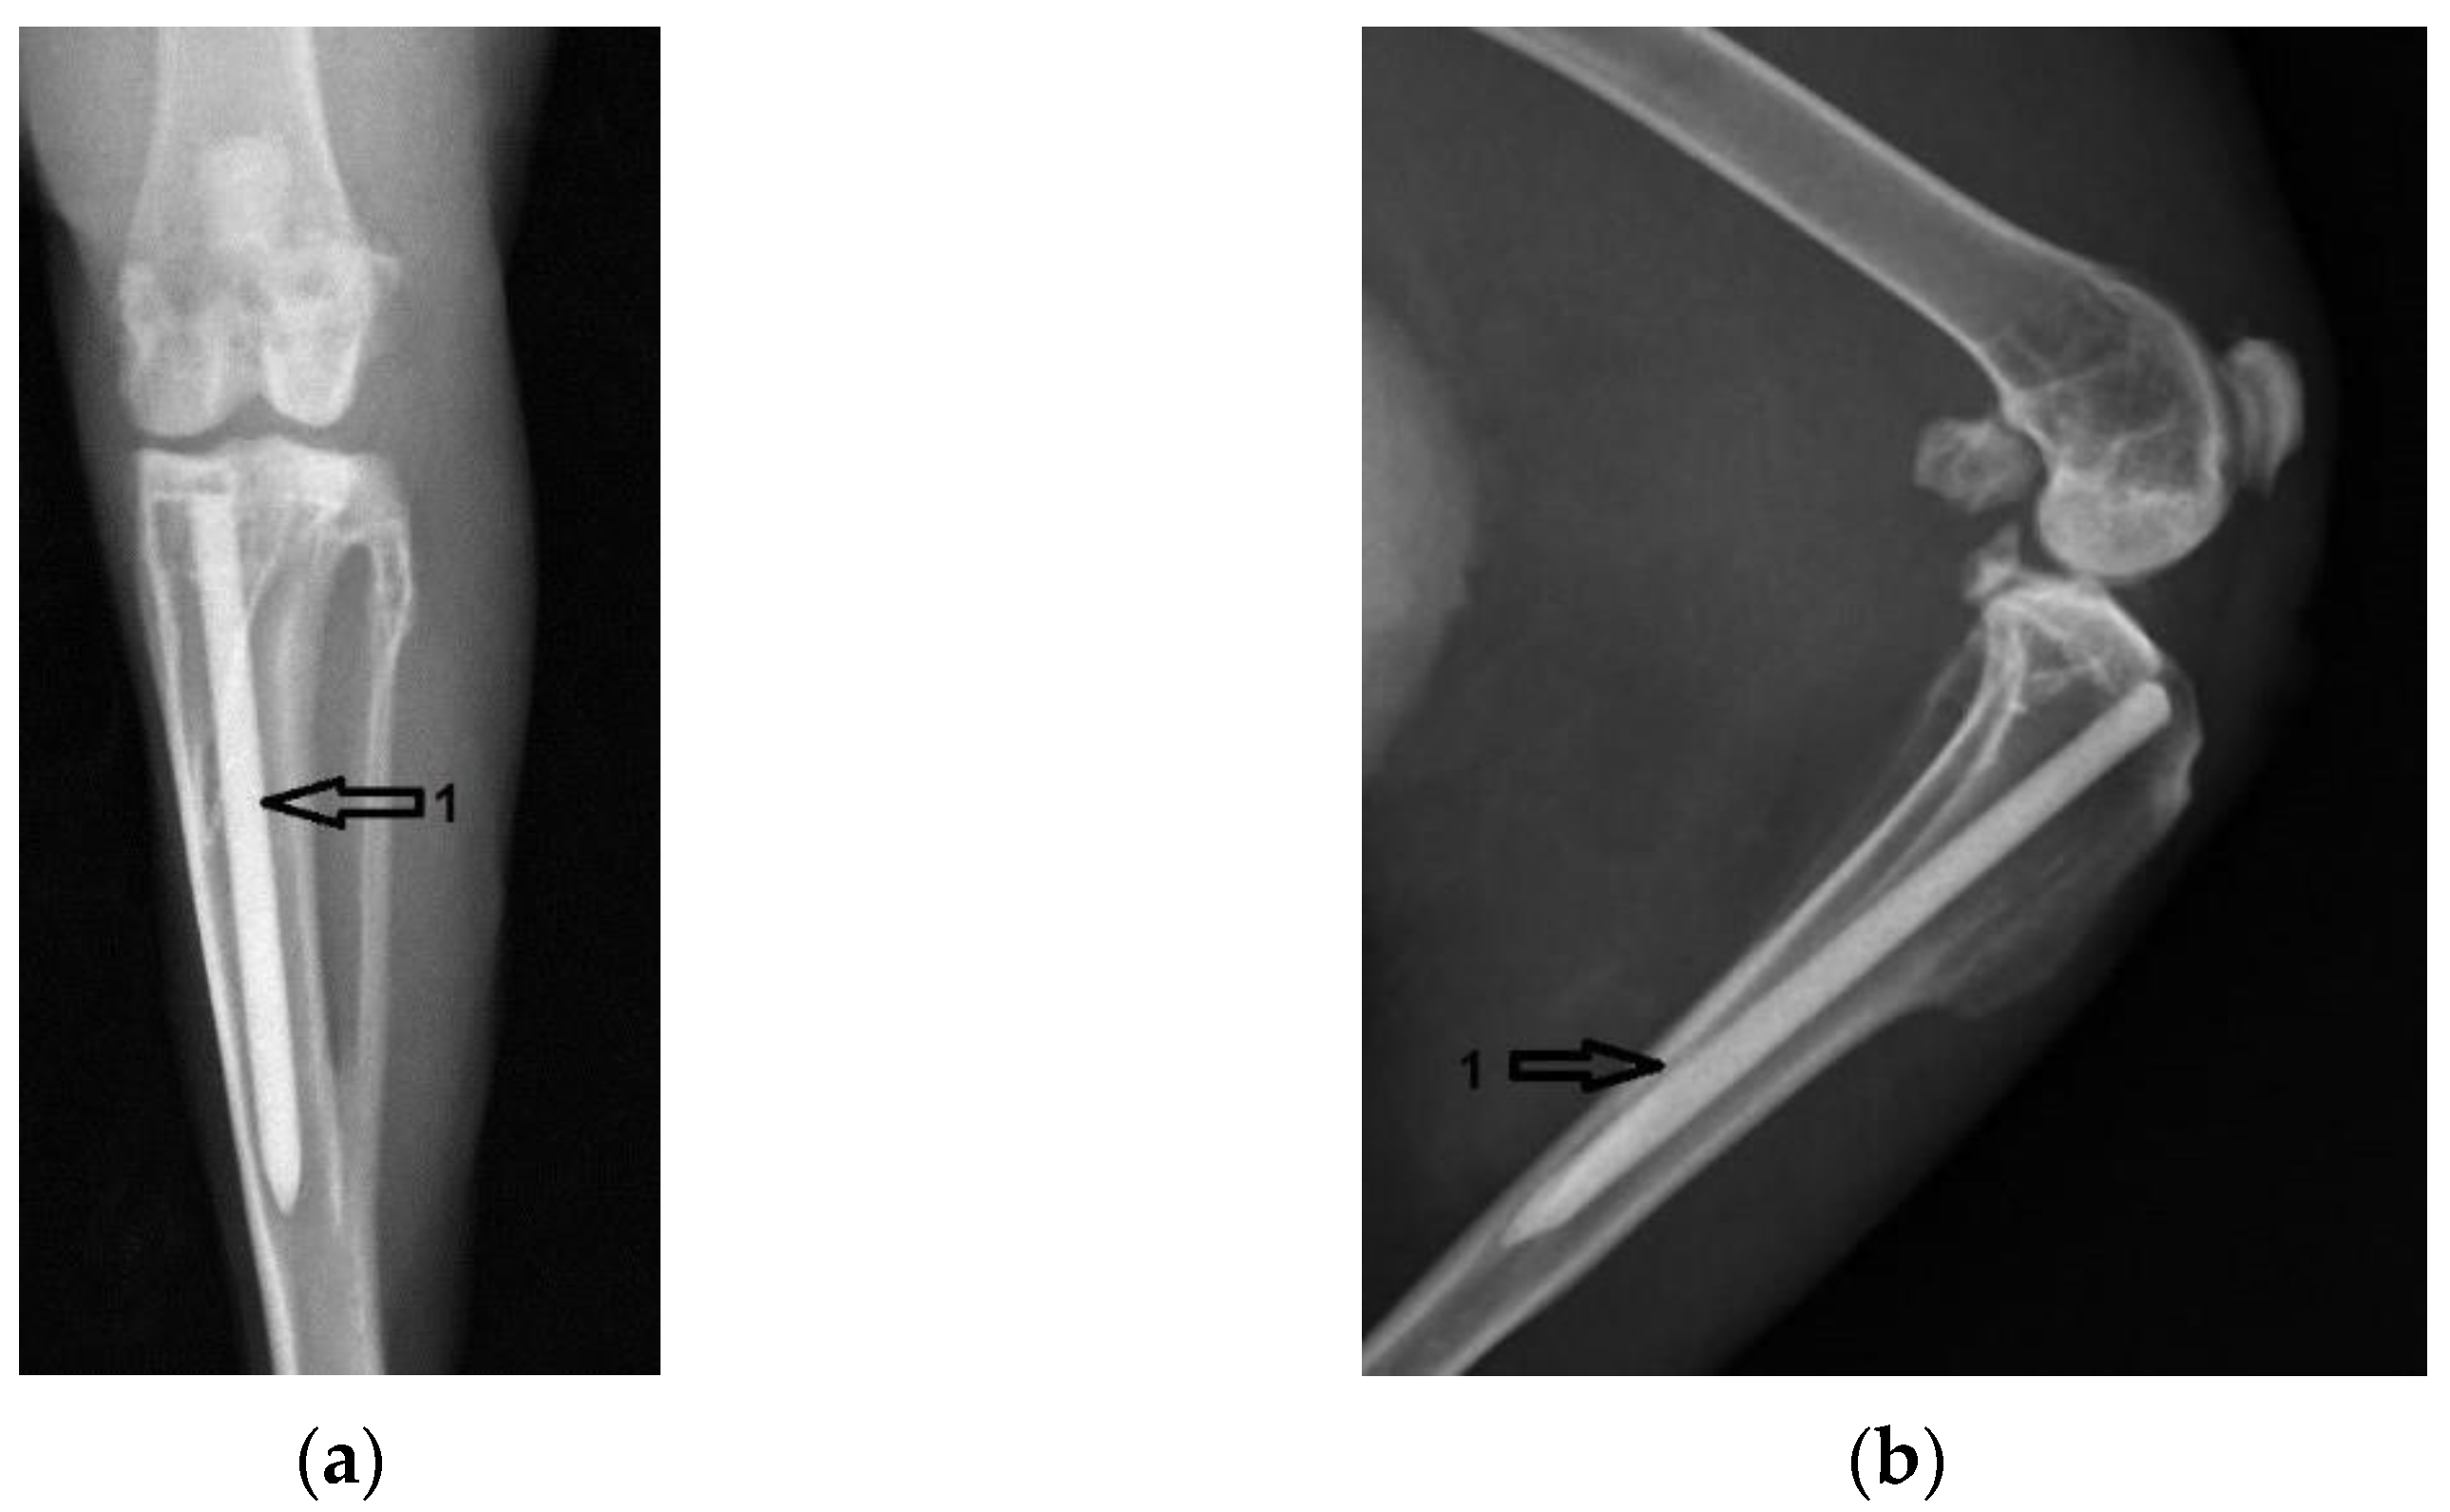

3.1. Radiological Followup